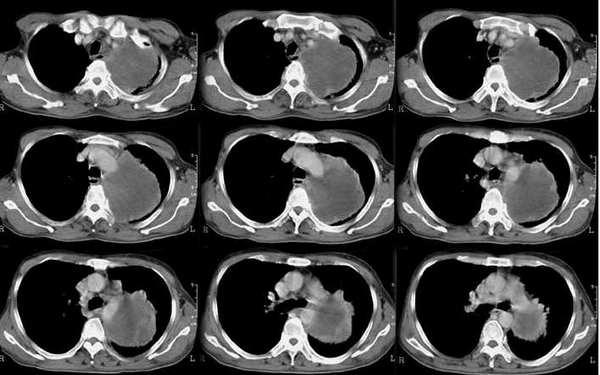

以下是引用乡医在2006-5-15 11:05:00的发言:[br]定位:来自纵隔[br]影象:与纵隔关系密切,类圆形,有膨胀感,有完整的壁及壁结节强化,内部密度均匀。[br]临床:男,60,胸不适半年,近有发热,无咳嗽咳血,平素体健无体检史。[br]影象意见:支气管囊肿合并感染。建议病理确诊。

以下是引用逸风在2006-5-15 17:08:00的发言:[br]ct所见各位老师描述很全面,不再赘述.补充一点,右侧镉肌局限性升高.[br]定位:左后上纵隔.从平片看,肿块外缘肺纹理呈弧形受压改变.横断扫描肿块在肺门周围靠后,肺门及气管位置未见明显移位.外周肺野未见明显阻塞性改变.[br]定性:恶性可能大.肿块边缘不光整,可见强化壁结节,内部有轻度不均匀强化密度,部分层面肿块与主动脉分界不清.右肺中叶小结节影.[br]诊断意见:左侧后上纵隔囊实性占位,考虑来源于神经源性肿瘤,恶性可能大.[br]建议:1.穿刺活检,明确诊断.2.b超右膈下检查,排外膈下病变.